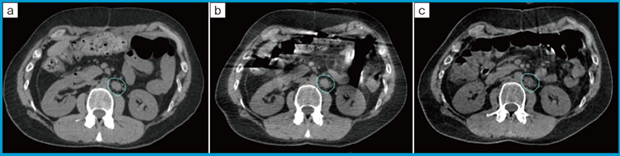

HyperSightは放射線治療業界最大のkilovoltage(kV)imagerが搭載されており,最大53.8cmのFOVを得ることができる。表1に,Halcyon version 3.0のCBCTシステムとHyperSightの比較を示す。HyperSightは最短わずか6秒でCBCTの撮影が可能であり,かねてより懸念されていた,息止め照射における患者負担およびスループット低下の大幅な改善が期待されている。CBCT撮影時間の短縮は息止め照射での利点だけでなく,図1に示すように,腸内ガスによるアーチファクトを低減することも可能である。さらに,画像再構成アルゴリズムにはiCBCT Acurosが導入されており,より鮮明な画像を取得することができる。画質の向上だけでなく,患者が治療寝台に滞在する時間も短くなるため,不快感や不安感を軽減できると考えられる。また,新たに金属アーチファクトを低減するアルゴリズムも搭載されており,頭頸部領域での歯科インプラントや骨盤領域における人工股関節を装着した患者の画質向上が可能となっている。

図1 Conventional CBCTとHyperSight CBCTの腸内ガスによるアーチファクトの比較

a:simulation CT b:conventional CBCT c:HyperSight CBCT

(画像提供:株式会社バリアンメディカルシステムズ)